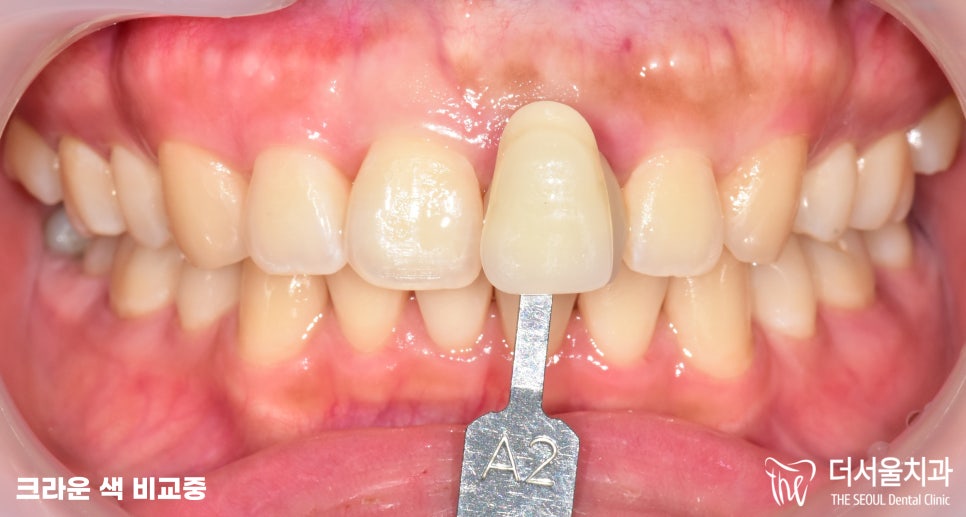

그 다음에 양 옆에 치아와

비슷한 색감의 크라운을

세팅할 수 있도록

보철을 가져다대어 비교를 해봅니다.

태평동치과 에선 A2, A3를 비교했을 때,

A2가 좀 더 적합하다 판단되어

해당 보철로 제작 후 세팅해드리기로 했습니다.

환자분 역시 A2가 더 낫다며

이것으로 하는게 좋겠다는 의견을 주셨습니다.

(카메라 플래쉬 때문에 조금 차이가 날 수 있으나,

실제로 보았을 때, 동일하게 맞춰드렸습니다.)